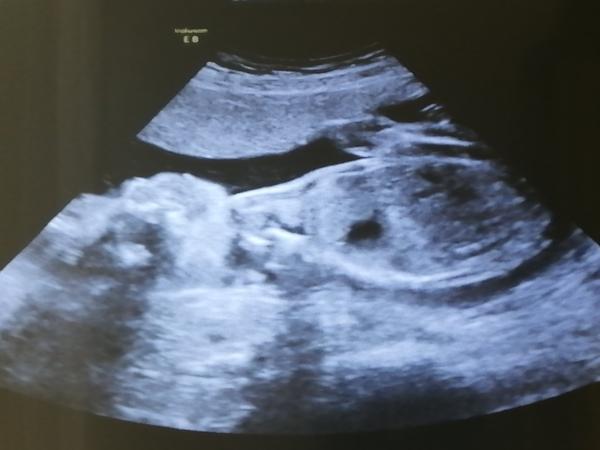

@lilian2111 ta fotka odpovídá tak desátému až 11tt těhotenství a proto je tak malý. Sijovy projasneni Ti nikdo teď neřekne protože to nikdo nevidí je to prostě jen malý tvorecek a to bílý je srdíčko. Nic jiného takže se neznepokojuj. Pokud Ti dr řekla že je srdeční akce tak je vše v pořádku. Maximálně nemusí odpovídat tydnama a může být o pár dnů mladší tudíž takovýhle drobeček a tudíž to dožene. My teď máme v bříšku takovyhodle chlapaka a to jsem dnes 24+1tt

@lilian2111 a je naprosto zdravý. Nenervuj se protože nenervujes jen sebe ale i to malý to cítí